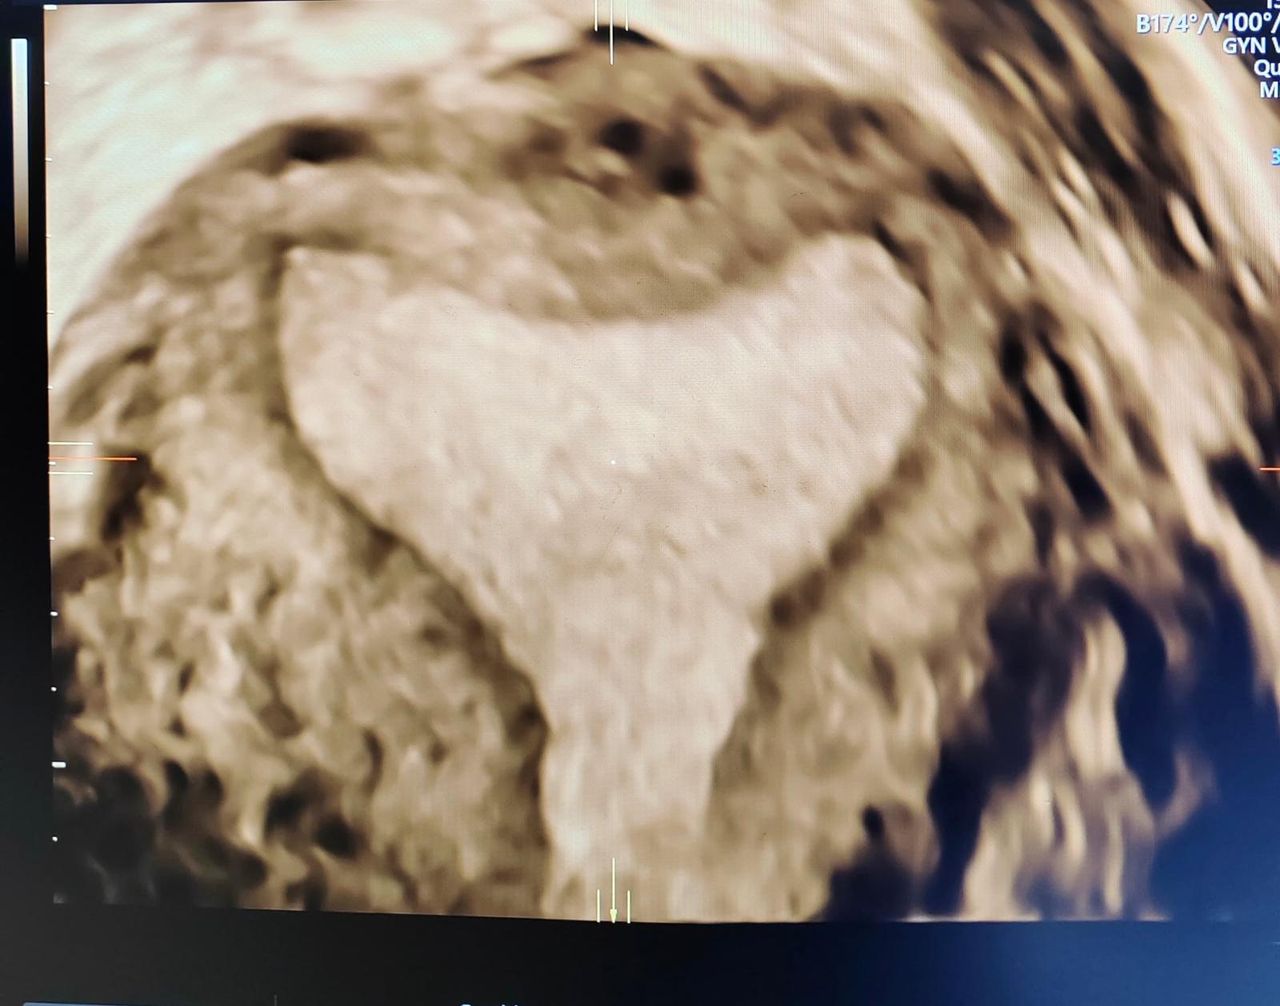

• Ecocardiografia fetale per lo studio approfondito del cuore del bambino

• Ecocardiografia fetale